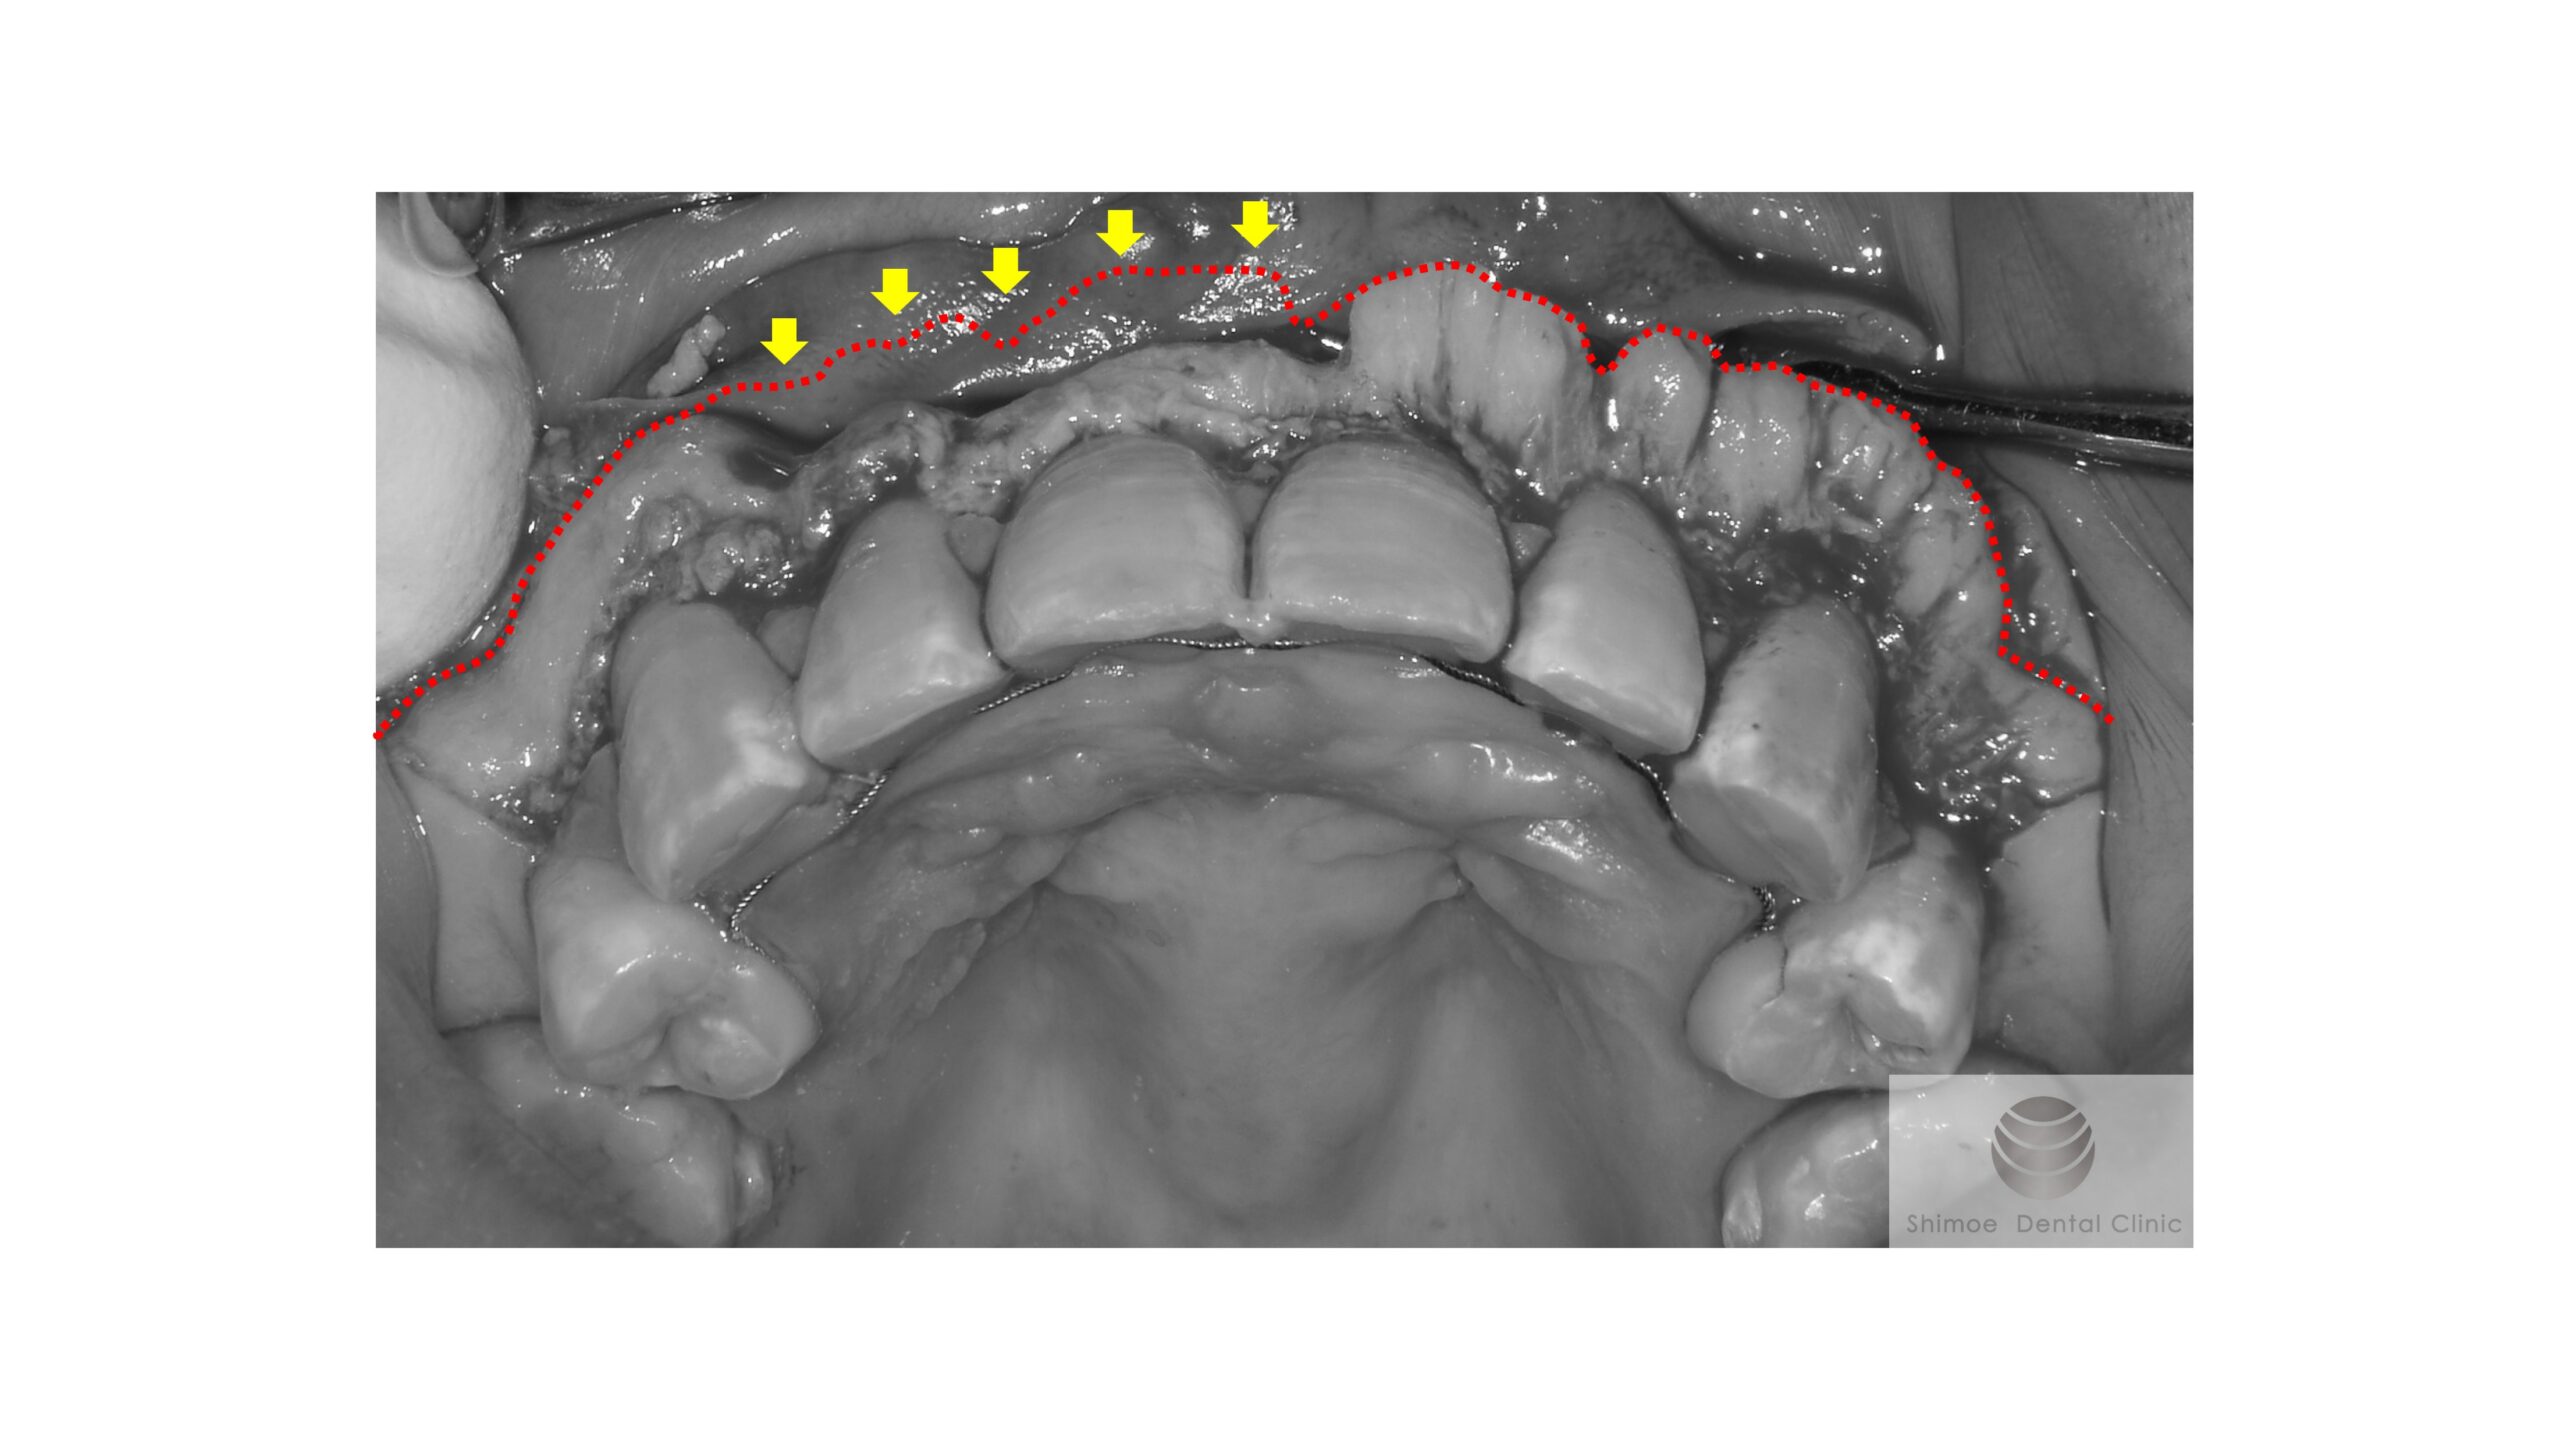

手術中

歯肉を剥離反転し、右側半分の骨隆起をある程度切除した時点の術中写真(グレースケール)

手術前の骨のラインを赤い点線で印しました。

右側半分を切除した時の状態です。黄色矢印で示す範囲の骨を切除しています。骨添加の具合がよく分かると思います。

切除時に注意しなければならないことは、骨の厚みです。歯根の方向と位置は1歯ごとにそれぞれ異なるので、それに伴ってどの程度骨が添加しているのか、1歯ずつ骨の切除量を見極め、切除していきます(審美的には切除したいが、審美面を求めすぎると、切除する歯槽骨量が増え歯根が露出したりするのでその歯自体の予後が悪くなるので注意が必要だし、外科を行うだけでも0.5mm程度は歯槽骨が吸収するので、色々な手術の経験も必要です)。

左側も同様に削合しました。